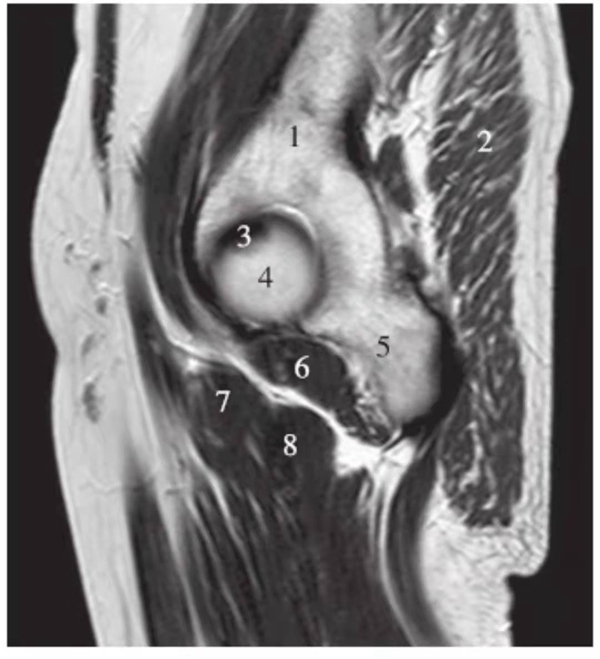

正常髋关节经股骨头中心层面T1WI像

1.臀中肌;2.髂骨;3.臀大肌;4.髂腰肌;5.股骨头骺线;6.股骨头;7.髋臼后唇;8.梨状肌;9.关节囊及髂股韧带;10.闭孔内肌;11.股方肌;12.大收肌